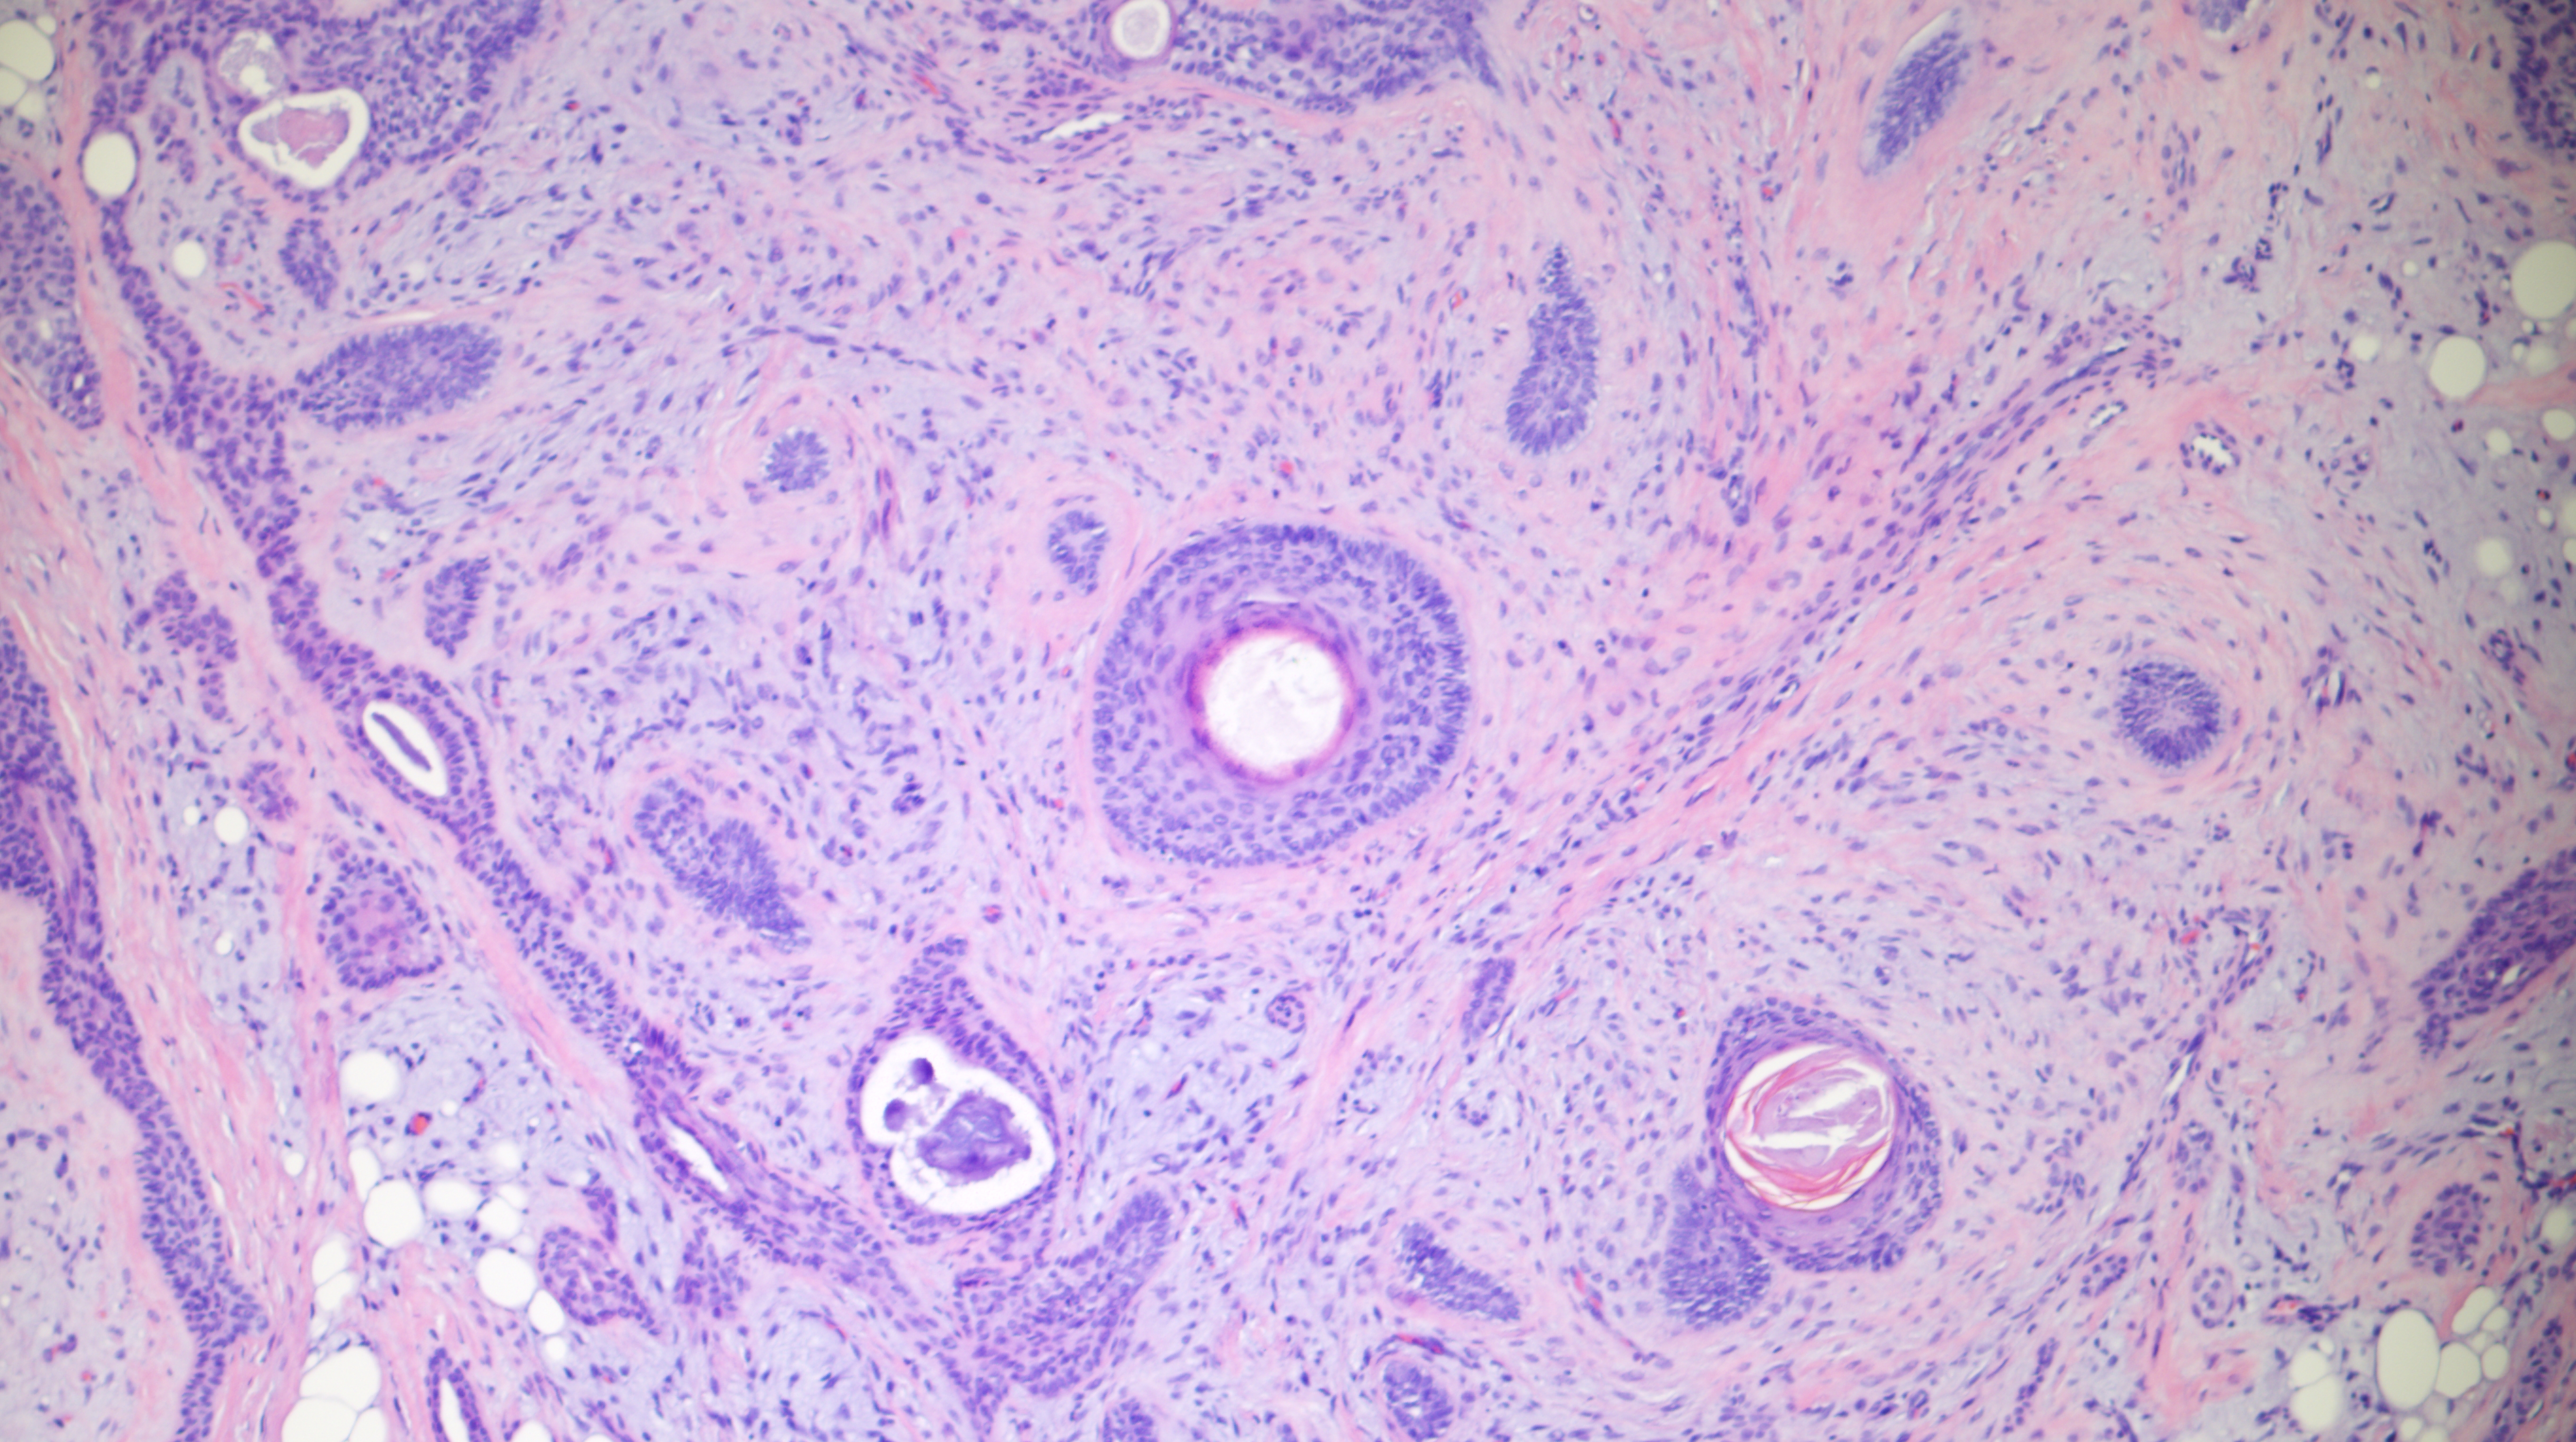

60-year-old man with an upper lip nodule.